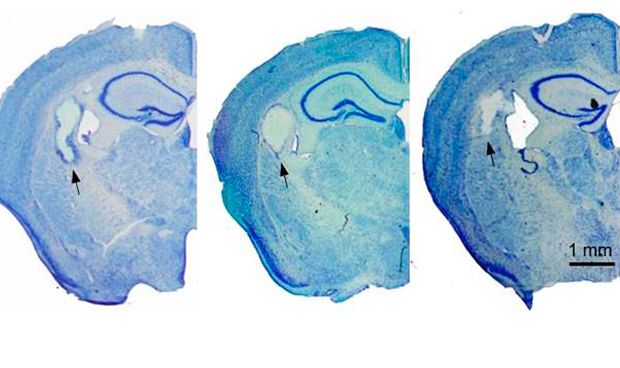

Los investigadores del Centro de Tecnología Biomédica de la UPM, inyectaron una disolución de fibroína de seda en el cerebro de ratones, gelificando dentro del tejido. Tras el trasplante, se evaluó a los animales mediante tests de comportamiento y registros electrofisiológicos para examinar la actividad eléctrica cerebral. “El implante produjo una respuesta inflamatoria mínima y los animales no manifestaron déficits cognitivos ni sensorimotores de relevancia”, apunta Laura Fernández García, estudiante de doctorado y primera firmante del trabajo.

“La fibroína de la seda es un material inerte, de baja immunogenicidad, que se utiliza desde hace años en diversas aplicaciones biomédicas como por ejemplo las suturas quirúrgicas. También se han realizado ensayos clínicos en implantes mamarios o para reconstruir la membrana timpánica”, destaca Daniel González.“Nuestro trabajo demuestra que este biomaterial, en un formato adecuado para el trasplante intracerebral (hidrogel) puede ser tolerado en el interior del cerebro de los animales”, añade.